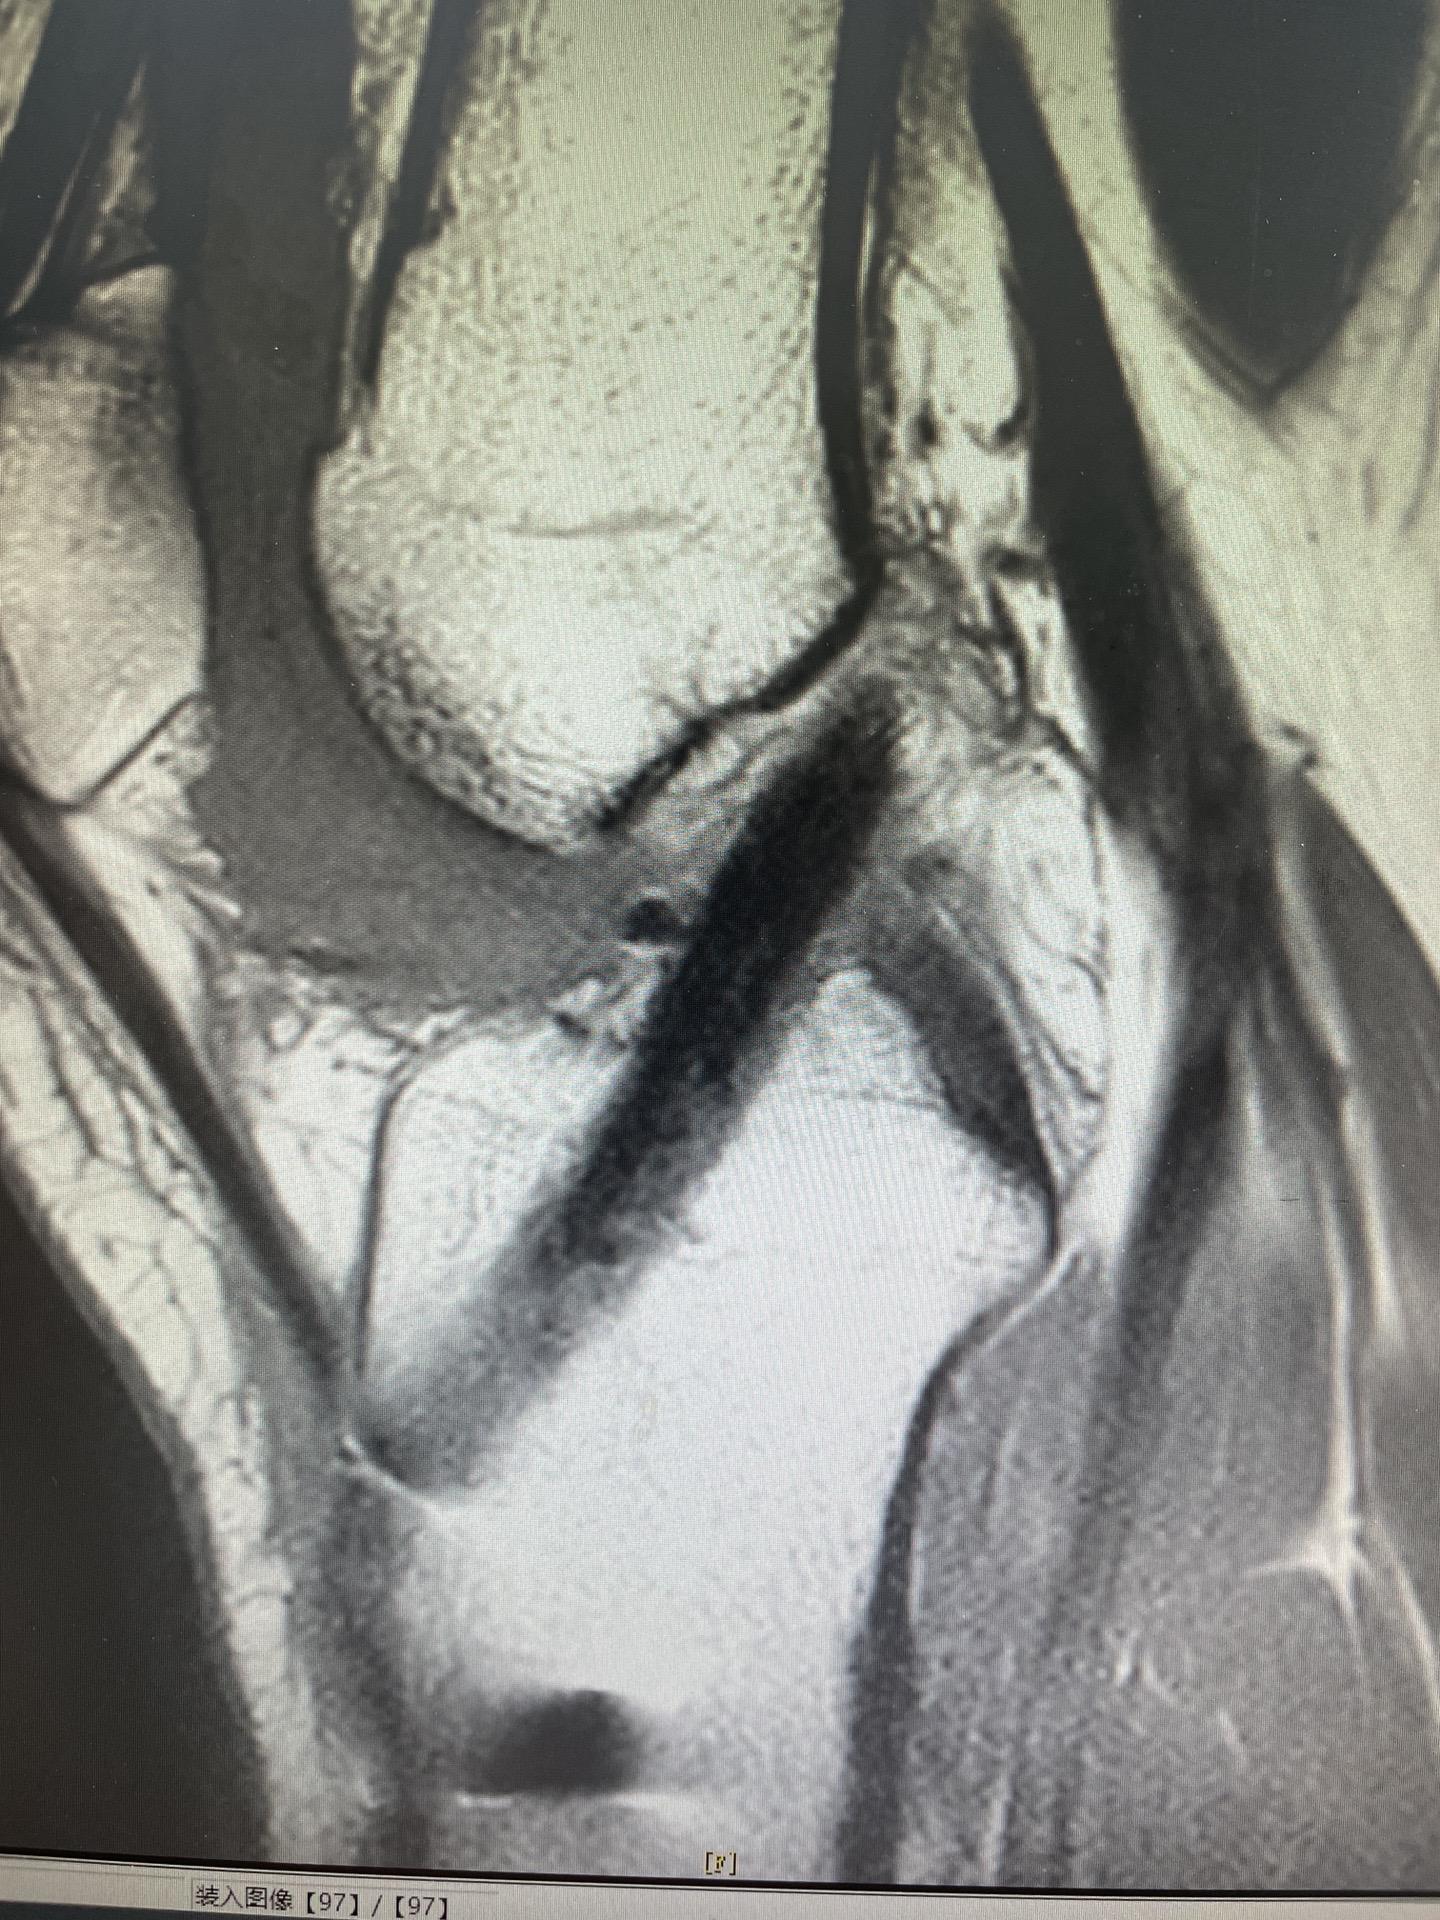

前交叉韧带重建。面对前交叉韧带的断裂,我们选择重建。希望这根强大的移植体,能为他撑起一片天,让他再次在运动场上放飞自我。前交叉韧带重建 前交叉